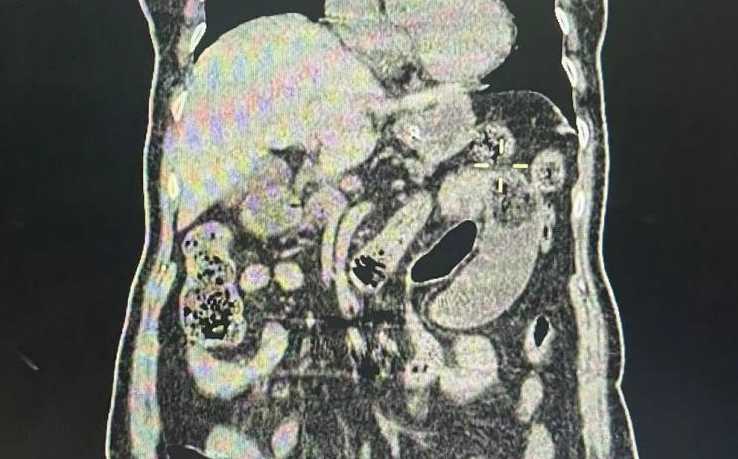

84岁的老人,因口服山楂、柿子后出现剧烈的腹痛腹胀,反复的恶心呕吐,到济宁市第一人民医院急诊科就诊,警觉性较高的接诊医生曹静立刻意识到老人很有可能得了胃石症,完善了腹部CT,证实老人因口服山楂柿子得了“胃结石”,让人意外的是“结石”已经通过胃腔排到了十二指肠。考虑到老人高龄,基础疾病较多,结石嵌顿在十二指肠水平段,外科会诊认为手术风险极大,首先去尝试胃肠减压、进食、口服碳酸氢钠等办法,希望小肠结石能溶解开。